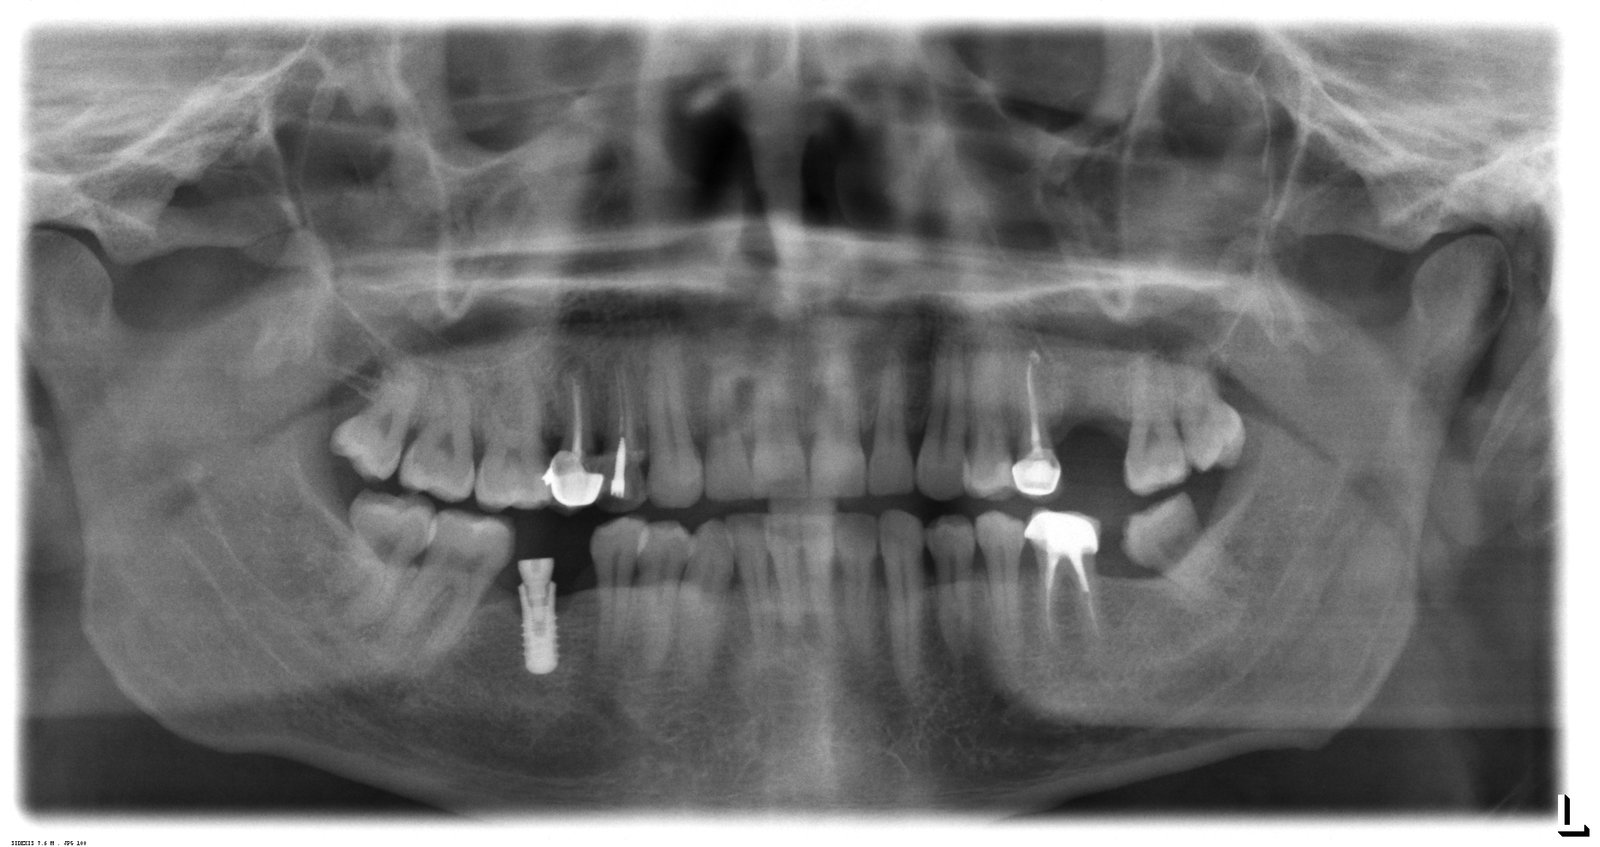

implante en piezas 46

buenos dias, querria ver si podeis ayudarme a saber que marca de implante es la de la pieza 46. gracias